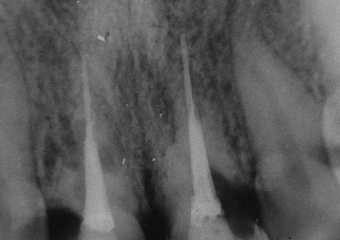

Reabsorção do 11 e 21, após 6 anos do reimplante